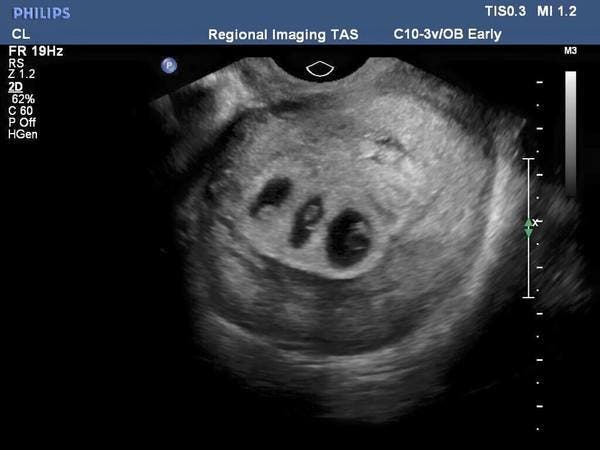

La grossesse étant à ses débuts, Chloé se rendit chez son gynécologue pour s’assurer du bon déroulement des événements, ne se doutant pas une seconde que le ciel lui réservait une surprise de taille. Ce n’est pas uniquement au quatrième enfant qu’elle devait s’attendre, mais au cinquième et au sixième également. Elle était en fait enceinte de triplés.

Au bout de sa 28e semaine de grossesse, Chloé se rendit encore une fois chez son gynécologue pour un suivi. Une séance dont le choc fut assez dur à supporter cette fois-ci.

Elle allait mettre au monde deux garçons et une fille, sauf que celle-ci présentait de sérieux problèmes de développement. Les médecins lui imposèrent alors un choix que nulle mère ne devrait endurer.

La fille allait probablement mourir sauf si une opération est effectuée, sauf que celle-ci mettait la vie des deux garçons en danger. Chloé devait soit laisser sa fille mourir et en sauver les deux autres, ou choisir de risquer la vie de ses triplés en passant par l’intervention chirurgicale.